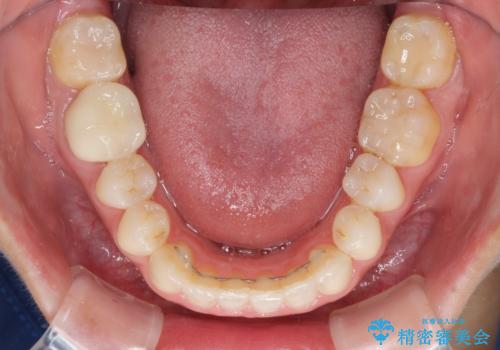

- 審美的ではない上の前歯とデコボコの下の前歯、歯茎が腫れている奥歯を気にして来院された患者様です。

根管治療の必要な歯がいくつかあるため、まずは根管治療を行い、その後インビザラインにて矯正治療を行うこととしました。

矯正治療後に前歯をセラミックブリッジに、奥の銀歯はセラミックインレーやPGAインレー(ゴールドインレー)にて補綴・修復治療を行うこととしました。